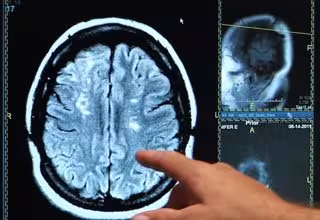

Archivo - Ictus, derrame cerebral, cerebro

Archivo - Ictus, derrame cerebral, cerebro - ONALD REAGAN UCLA MEDICAL CENTER - Archivo